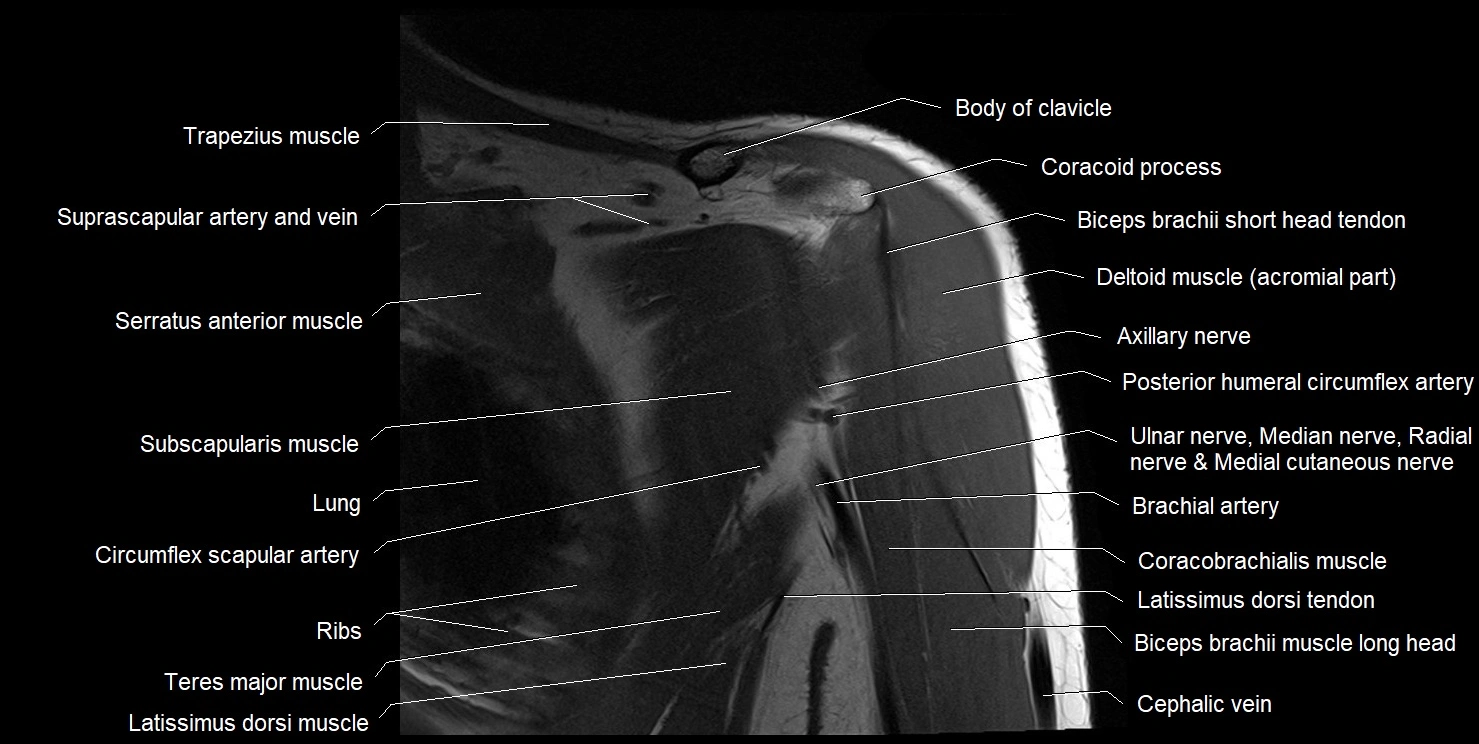

MRI images

image